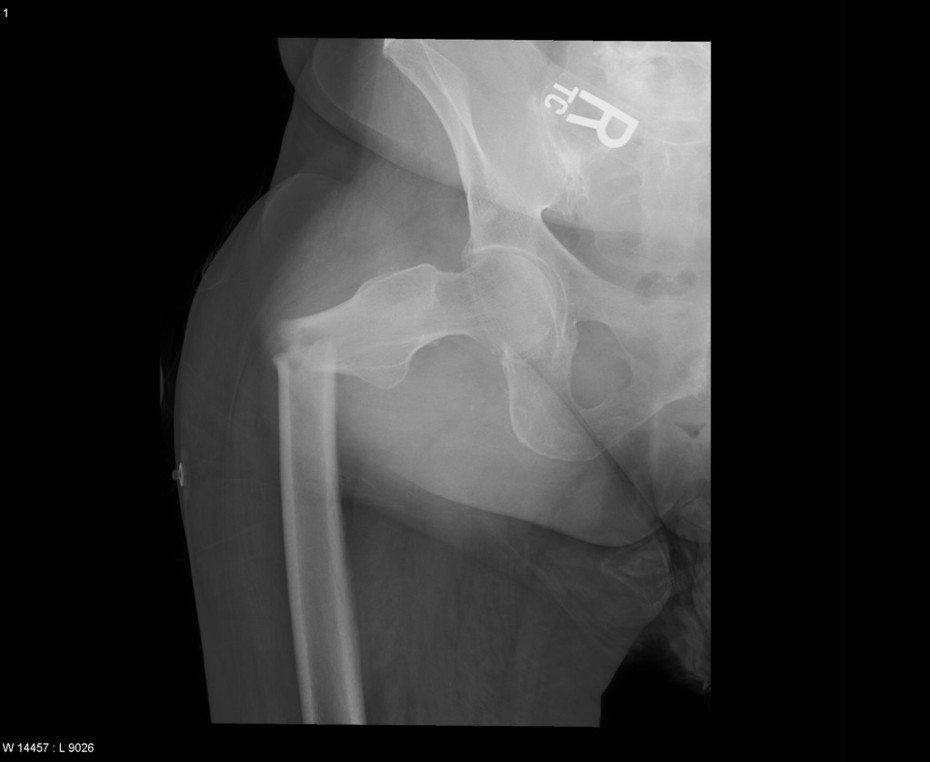

Diagnosis: Right femoral fracture with significant angulation

Modality: X-Ray

Credit: Case submitted by Dr. Ronald Smith (Radiologist) to radRounds Radiology Network